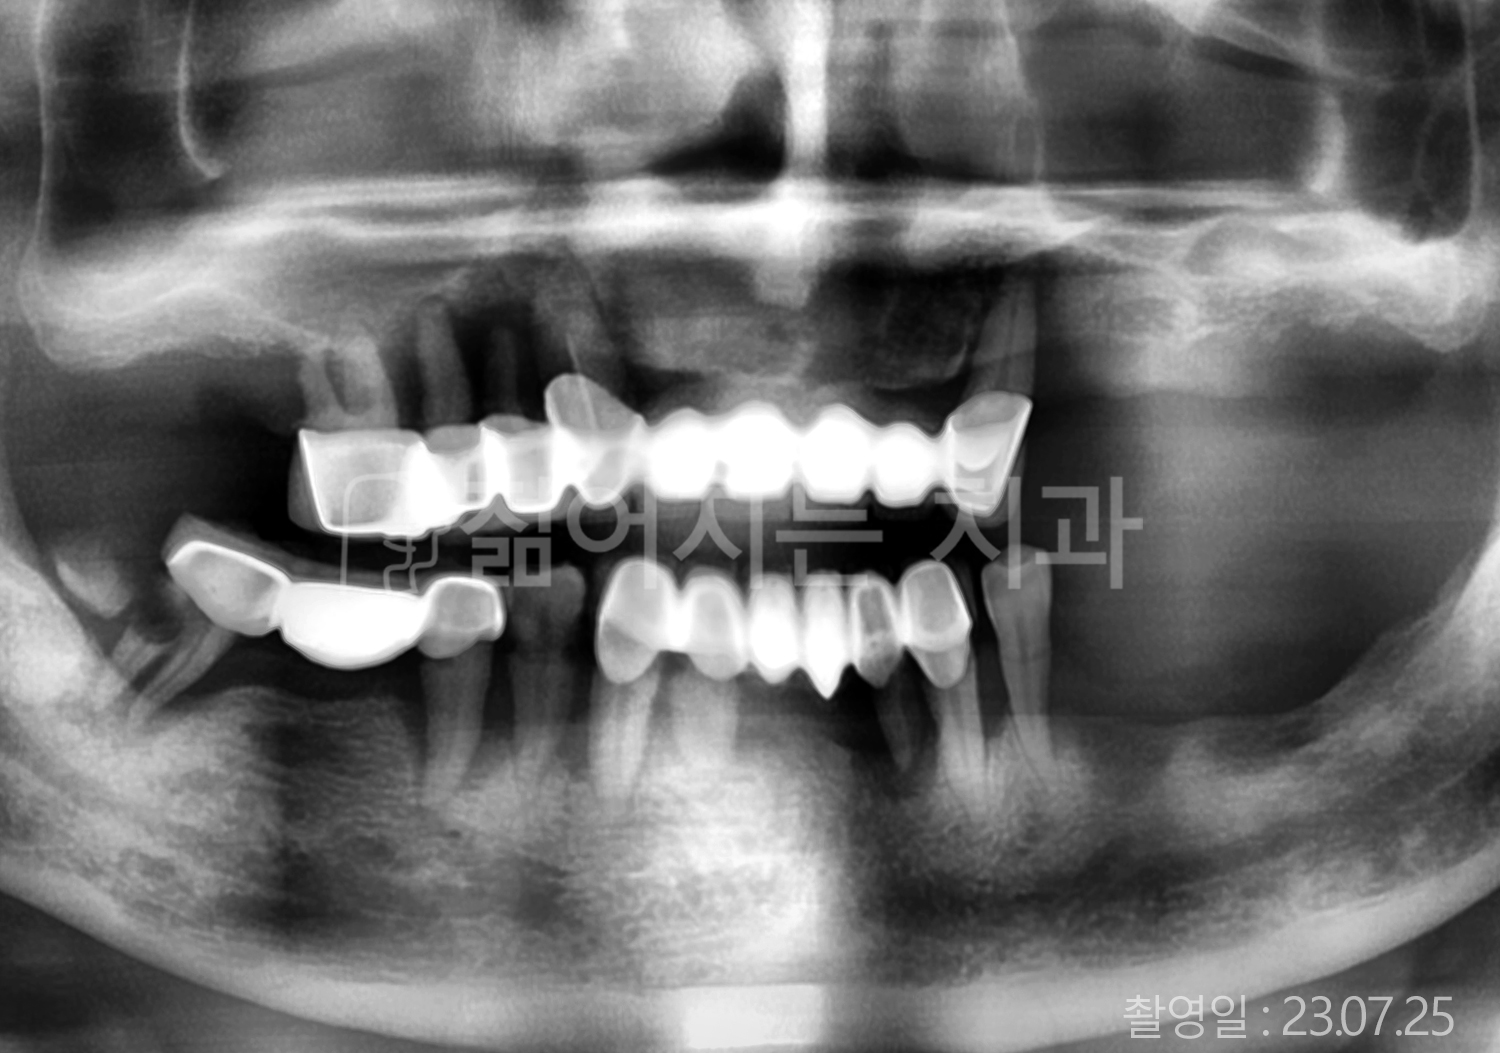

• 60대 전체치아 10개 이상 임플란트